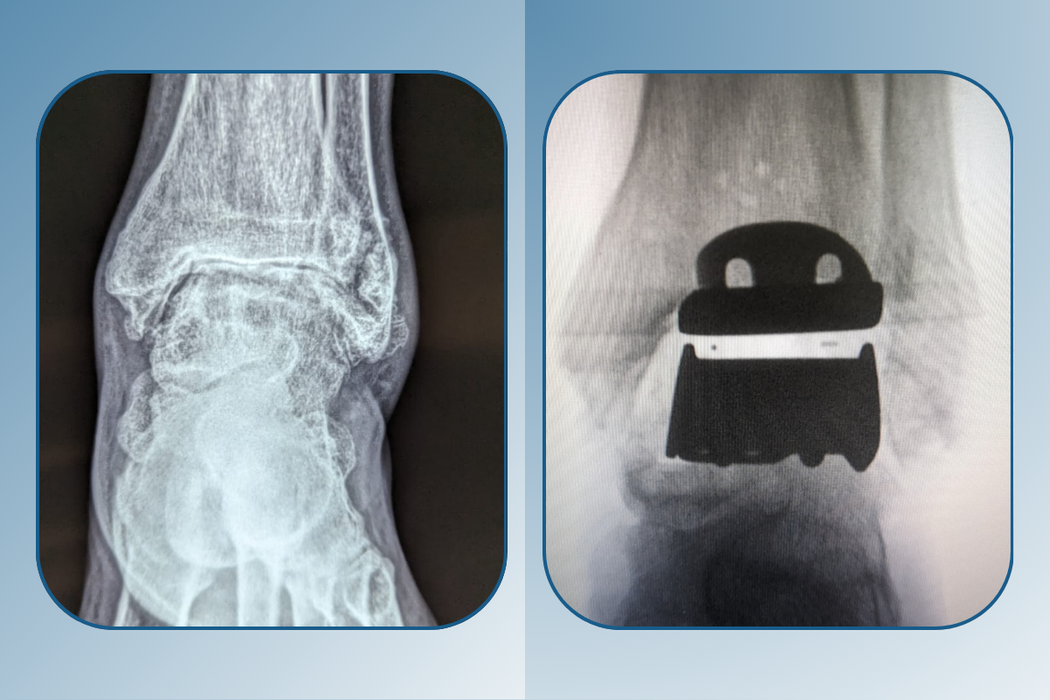

The ankle joint is taken out and replaced with a metal and plastic device in a total ankle replacement. Ankle replacement surgery aims to restore the patient's range of motion while reducing pain, allowing them to regain full function when they exercise.

Amble Foot & Ankle Centre proudly announces that we are the leading orthocare experts in Indian medical history. Dedicated to providing innovative medical treatment in an effective time, Amble Foot & Ankle Centre Ahmedabad fosters an environment of consistent excellent growth with the help of the most renowned doctors in the field. Dr. Dhimant Patel, an esteemed orthopedist, made history in Ahmedabad by completing the first ankle replacement procedure.